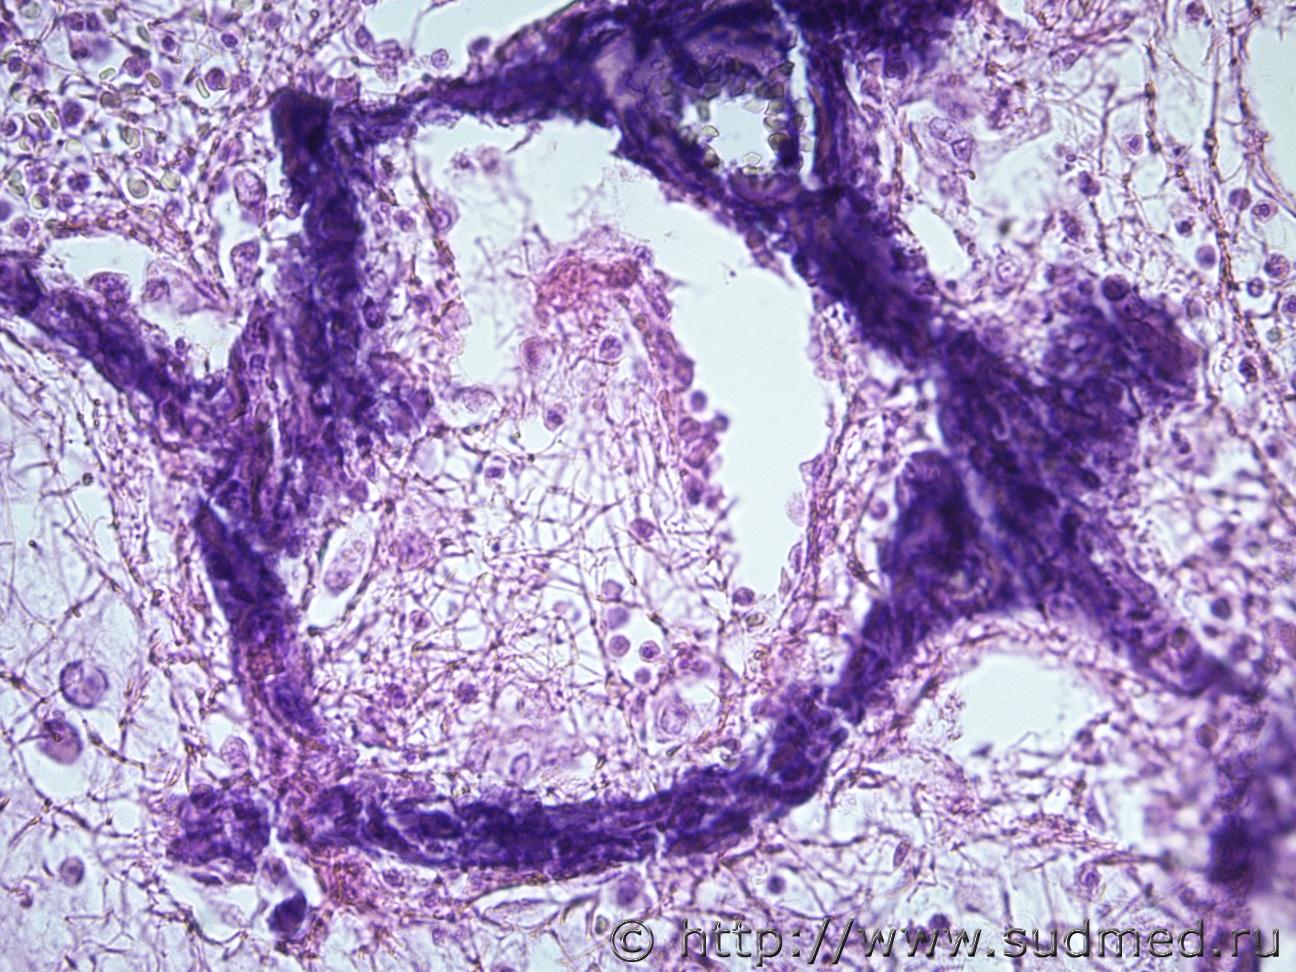

Ув. коллеги, нужна помощь, что это за заболевание легких? В атласе патологическая анатомия легких, нет не чего похожего. Это какое то диффузное паренхиматозное заболевание?. Жен 46 лет. Макро- Воздушность ткани верхних долей легких снижена, легочная ткань сиреневой окраски, образования диффузного характера беловато-сероватого цветы, плотные. По всем препаратам межальвеолярные перегородки инкрустированы известью. В просвете альвеол фибрин, лейкоциты, макрофаги.

Медик В просвете альвеол в основном мицелий грибов. 12.08.2019 - 21:49

Медик На втором фото похоже на ИФА (такие изменения могу... 12.08.2019 - 21:56

Медик Петрификаты в межальвеолярных перегородках могут б... 12.08.2019 - 22:04

доктор морфолог Уважаемый Медик, как всегда в точку попадает. Это ... 14.08.2019 - 20:49